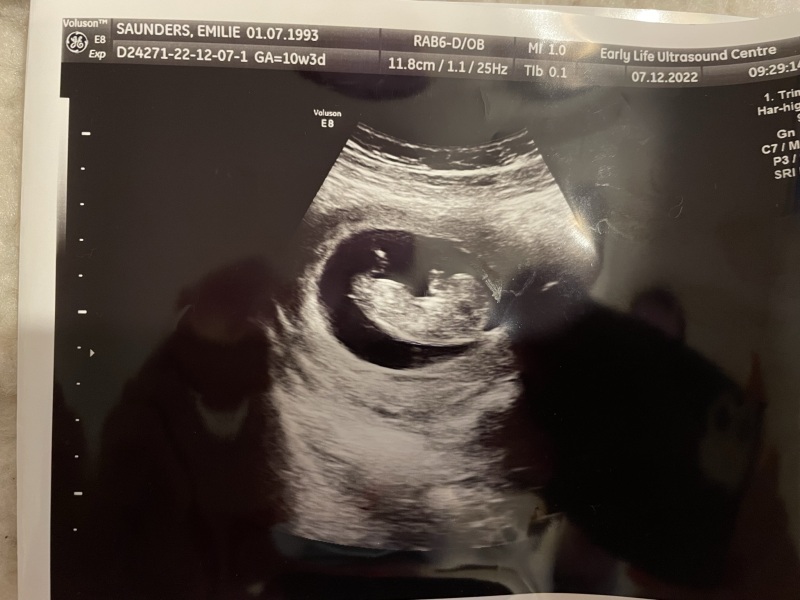

BOY OR GIRL?❤️💙

What do we reckon???